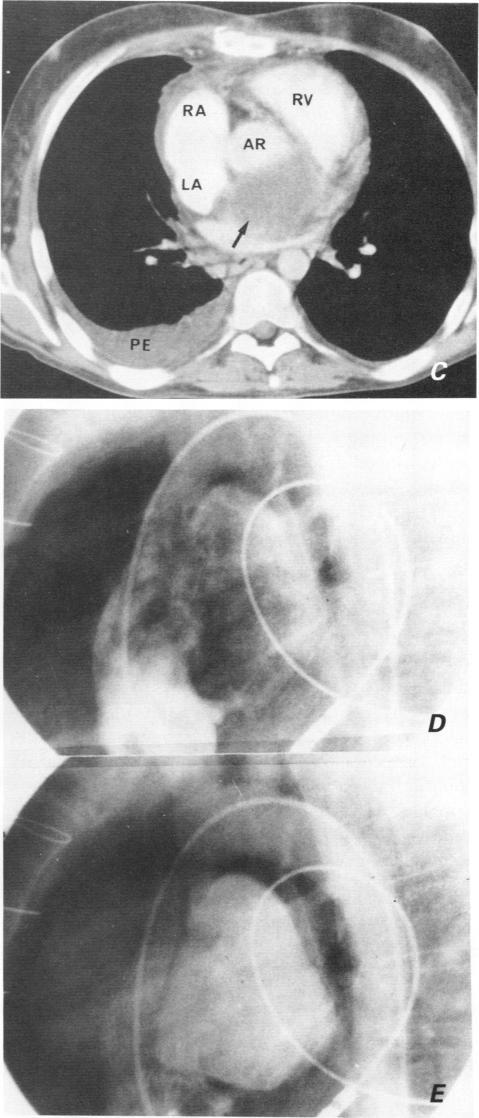

After cardiac transplantation, bacterial mediastinitis is a rare but dangerous early complication. Of the 113 patients who underwent heart or heart-lung transplantation at our hospital from August 1981 to April 1989, 8 developed purulent mediastinitis. Treatment involved surgical débridment, local irrigation, drainage, and high-dose systemic antibiotics. No patient died of an acute mediastinal infection. In 2 cases, however, chronic mediastinitis led to the formation of a huge mycotic aneurysm of the ascending aorta. Eleven days after surgical intervention for rupture, 1 patient died of aneurysmal rerupture; the 2nd patient remains well 16 months after prosthetic replacement of the ascending aorta and reconstruction of the necrotic proximal portion of the left coronary artery with a saphenous vein patch.

心脏移植后,细菌性纵隔炎是一种罕见但危险的早期并发症。1981年8月至1989年4月在我院接受心脏或心肺移植的113例患者中,有8例发生了化脓性纵隔炎。治疗包括手术清创、局部冲洗、引流以及大剂量全身应用抗生素。没有患者死于急性纵隔感染。然而,有2例患者发生慢性纵隔炎,导致升主动脉形成巨大的霉菌性动脉瘤。1例患者在手术干预破裂后11天死于动脉瘤再次破裂;第2例患者在升主动脉人工置换并用大隐静脉补片重建左冠状动脉坏死近端后16个月情况良好。